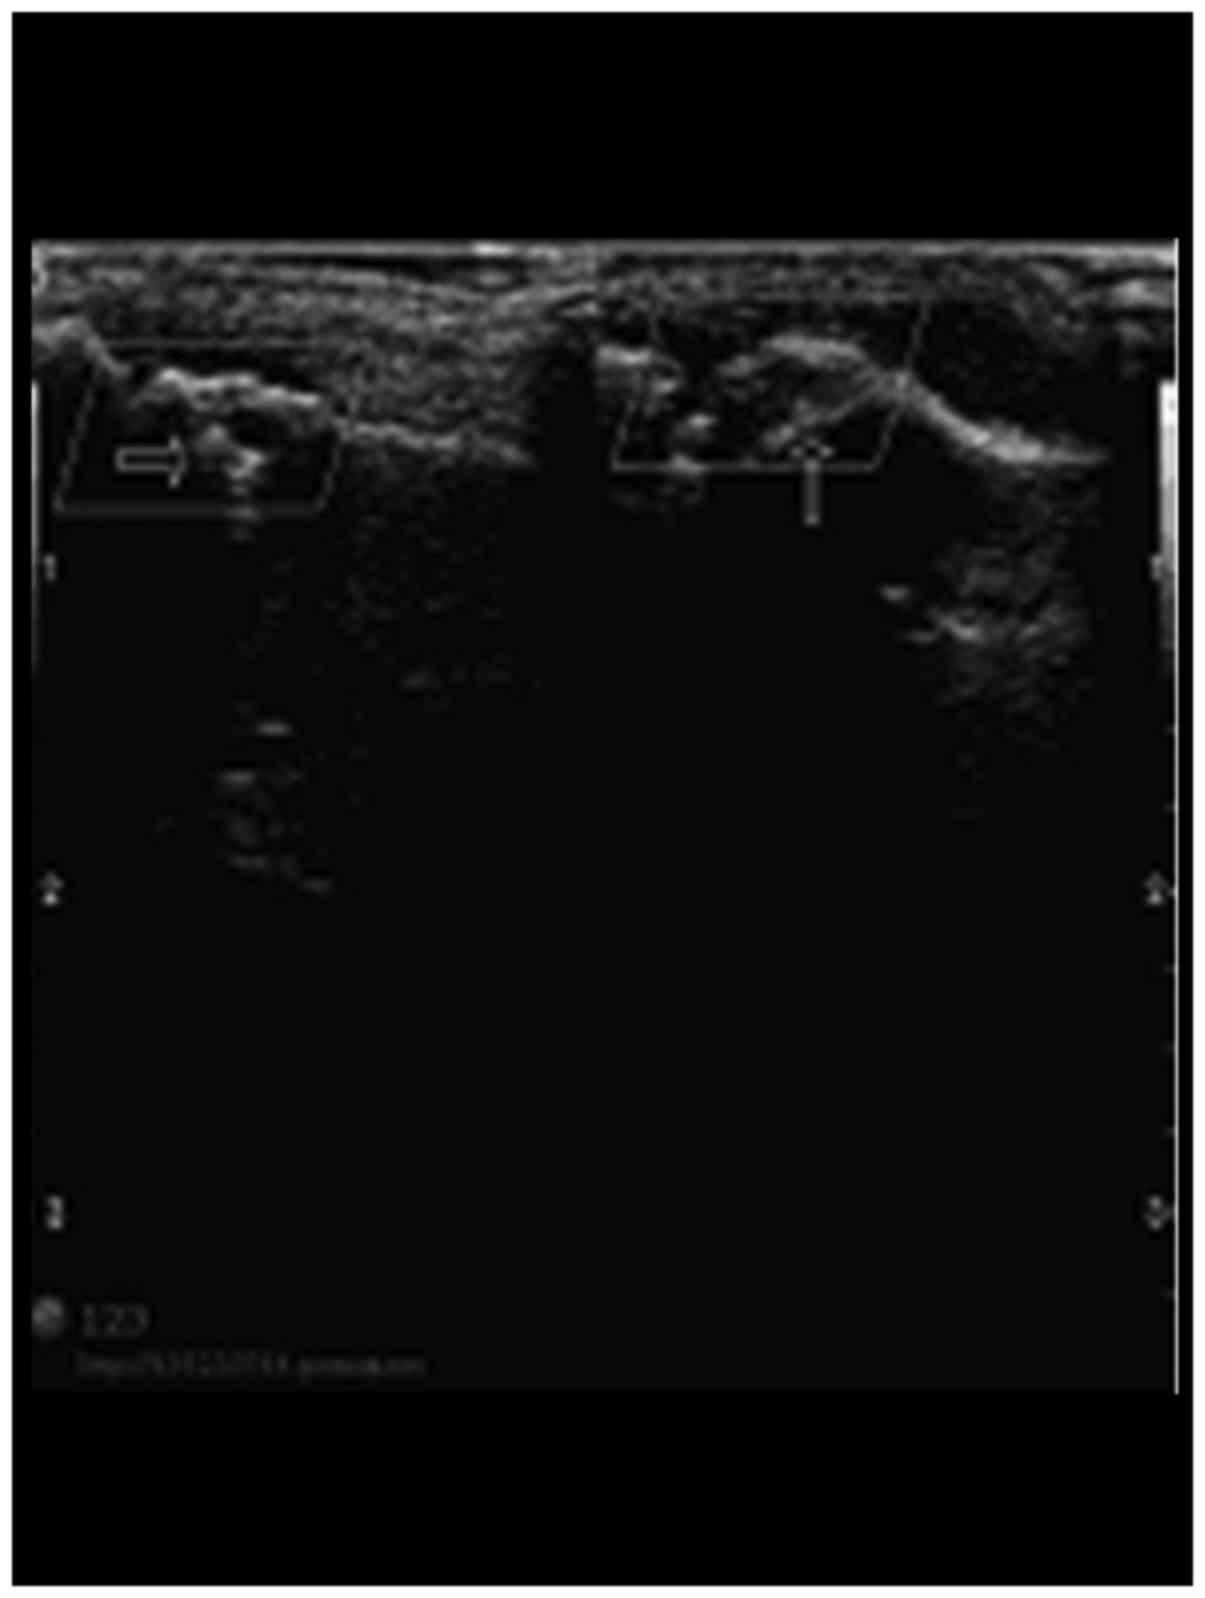

Figure 1.

The high-frequency color Doppler ultrasonography manifestation of articulationes interphalangeae of digitus medius of the patients with bone erosion.

Comparison of the HCDU examination

HCDU examination results showed that the articulationes interphalangeae of digitus medius in patients with bone erosion in the study group showed articular surface roughness, and continuous interruption at the margins (Fig. 1). The detectable blood signal rate of articulationes interphalangeae in the study group was 65.7%, and blood signals were detected inside the articulationes interphalangeae and at the margins (Fig. 2). The eroded cartilage and subcortex medullary bone substance in the study group had lower echogenicity and irregularly defined tumor-like lesion. The internal echo was uneven (Table I).